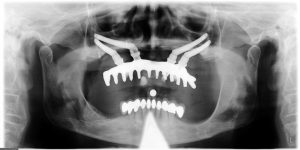

L’impianto zigomatico, invece, consente di impiantare subito le protesi fisse dell’arcata superiore, senza dover eseguire prima un innesto di osso. Le viti usate hanno maggiore lunghezza e possono essere, quindi, inserite direttamente nell’osso dello zigomo.

Un altro punto di forza di questo tipo d’impianto è la stabilità, conferita alle protesi fisse, dai perni immessi nello zigomo invece che nell’alveolo. La masticazione risulta più agevole e sicura, la sensazione di benessere è più netta.

Questa tecnica viene usata fin dagli anni ’80 in Svezia ed in pratica l‘impianto zigomatico va ad ancorarsi nelle ossa dello zigomo, sostenendo e dando una maggiore stabilità ai denti. Secondo gli studi scientifici internazionali l’impianto dentale zigomatico riscontra una percentuale di riuscita del 98-100% dei casi.